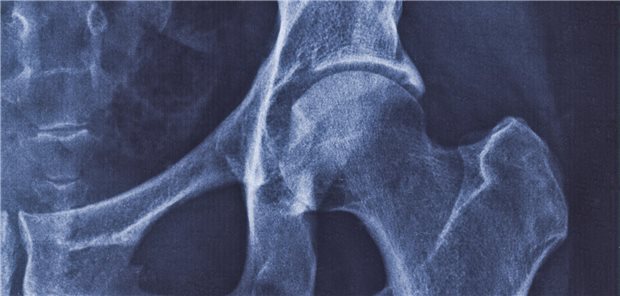

Die Darmgesundheit zu fördern, kann positiv auf eine Coxarthrose wirken.

© ss404045 / stock.adobe.com

Veranstaltung von Theralution / Medice

Auch Arthrosen haben etwas mit dem Darm zu tun